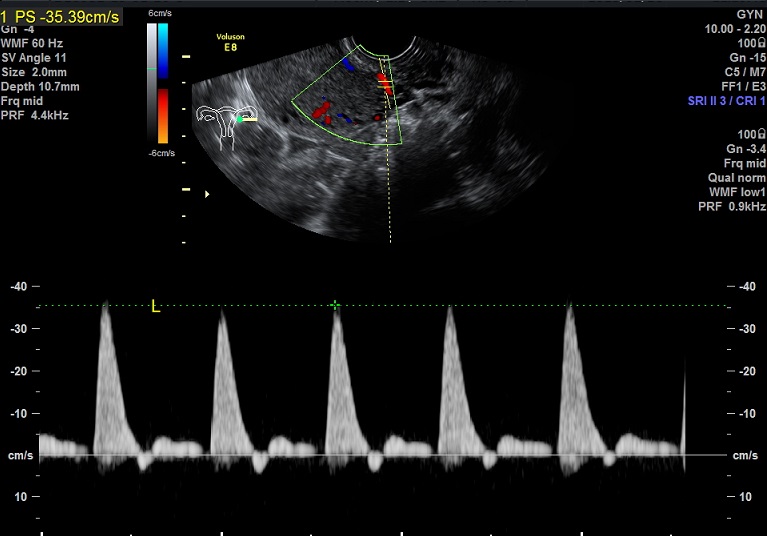

| 女性,25岁,继发性不孕1年余,难免流产4次。 | ||

2015-1-26 月经第23天检查 黄体期 |

2015-1-26图示